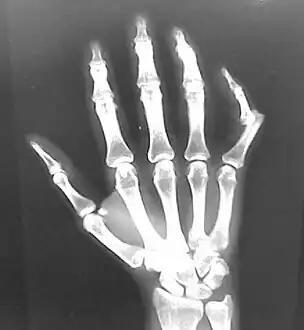

Dislocation of the left index finger

Radiograph of right fifth phalanx bone dislocation

Radiograph of left index finger dislocation